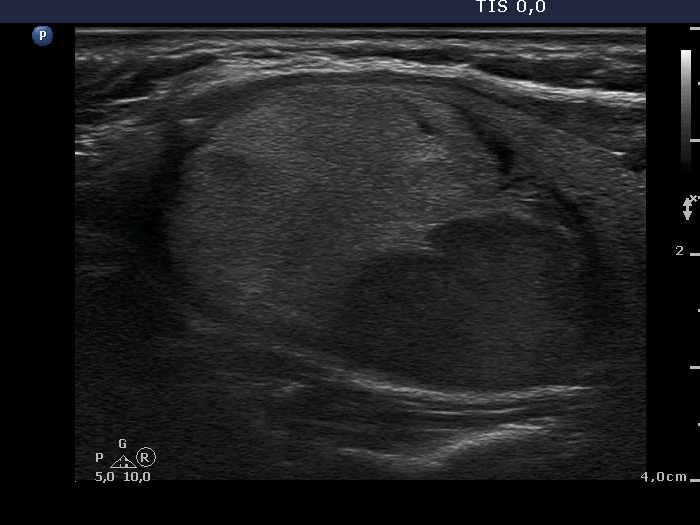

The echogenicity of the nodule - case 2158 (ultrasonographic picture 3)

Right lobe, another longitudinal scan.